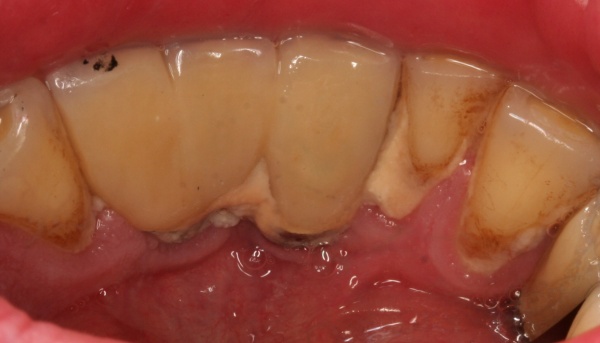

In der prächirurgischen Phase muss ein besonderes Augenmerk auf die prognostische Einschätzung der parodontalen und dentalen Situation gelegt werden. Dabei ist insbesondere auf die allgemeinmedizinische und spezielle dentale Anamnese zu achten. Bornstein et al. (2009) untersuchten den Einfluss von Allgemeinerkrankungen auf die Periimplantitis. Unter anderem Safi et al. (2009) wiesen auf die Bedeutung einer Parodontitishistorie hin. Aber auch die Lebensgewohnheiten des Patienten haben einen entscheidenden Einfluss (Tabakkonsum, ungenügende Mundhygiene, fehlende Nachsorge [Heitz – Mayfield & Huynh – Ba 2009]) (Abb. 3).

Diagnostische Parameter für die Beurteilung der dentalen und der periimplantären Zustände sind die Plaqueakkumulation, die Sondierungstiefen des Zahnes und des Implantates, Bluten auf Sondierung, Suppuration und der radiographische Knochenverlust (Salvi & Lang 2004). Unabdingbar ist im Minimum eine Sechspunktmessung (Sondiertiefen und klinischer Attachmentlevel). Immer wieder hört man von der Befürchtung, dass durch ein Sondieren des Implantates dieses geschädigt wird. In einer histomorphometrischen Studie an Hunden haben Etter et al. (2002) die Heilung des periimplantären Weichgewebes nach standardisiert klinischem Sondieren untersucht. Die Heilung des Epithelansatzes nach Sondierung des gesunden periimplantären Gewebes ist nach fünf Tagen abgeschlossen. Erfahrungsgemäß ist bei besonders aufmerksamem und vorsichtigem Sondieren ein äußerst geringes Verletzungsrisiko gegeben. Auch diese Techniken können in einem Praktikum bei einem Parodontologen aufgefrischt werden.